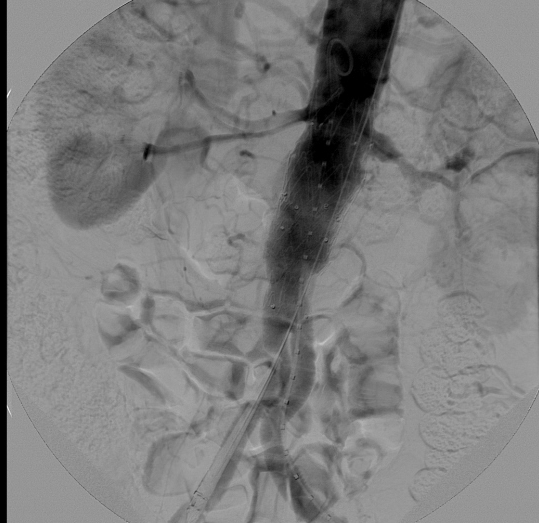

نجاح ثالث عملية لإصلاح الشريان الأورطي فى المستشفى السعودى الألمانى بالرياض

نجح فريق الأشعة التداخلية بالتعاون مع قسم جراحة الأوعية الدموية فى المستشفى السعودي الألماني بالرياض، في إجراء عملية لإصلاح الشريان الأورطي عن طريق تركيب دعامات بواسطة القسطرة التداخلية "إيفار" عن طريق فتحة صغيرة فى الجلد.

ويعتمد الأسلوب الجديد على تصليح التمدد بالشريان الأورطي عن طريق تركيب دعامة صناعية من خلال قسطرة يتم إدخالها من شرياني الفخذين، مما يعجل بالشفاء ويقلل المضاعفات الجراحية والنزيف ومدة البقاء تحت الرعاية المركزة خاصة لبعض الحالات التي لا تسمح حالتهم البدنية والصحية بالتخدير فضلاً عن اختصار زمن وتكلفة العلاج مقارنة بالعمليات الجراحية التقليدية، حيث كان في السابق يتم إجراؤها عن طريق الشق الجراحي وما يعقبه من آلام شديدة للمريض ومضاعفات جانبية وطول فترة البقاء في المستشفى.